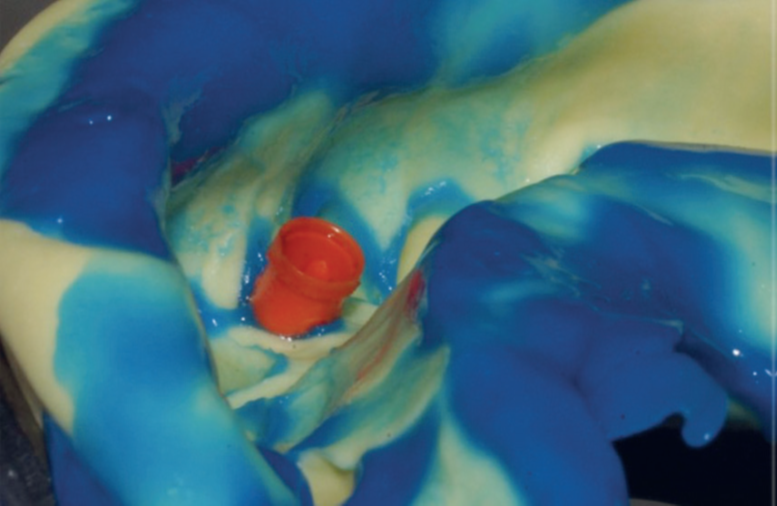

Assim, um coping de titânio (Implacil De Bortoli) foi utilizado para a confecção da restauração provisória instalada em seguida, permanecendo no local por 15 dias para formação do novo perfil de emergência no elemento 41 (Figura 6). Então, o provisório foi removido, o novo perfil de emergência foi constatado e o transferente de moldagem correspondente ao tamanho do pilar foi posicionado para a execução do procedimento (Figuras 7 e 8). A moldagem foi realizada com silicone de condensação (Optosil e Xantopren, Kulzer) e, após a polimerização do material, o molde foi retirado arrastando consigo o transferente de moldagem (Figura 9). O análogo foi inserido no transferente e o molde foi vazado com gesso especial tipo IV (Durastone), sendo realizada a confecção do coping metálico no laboratório (Figuras 10 e 11).